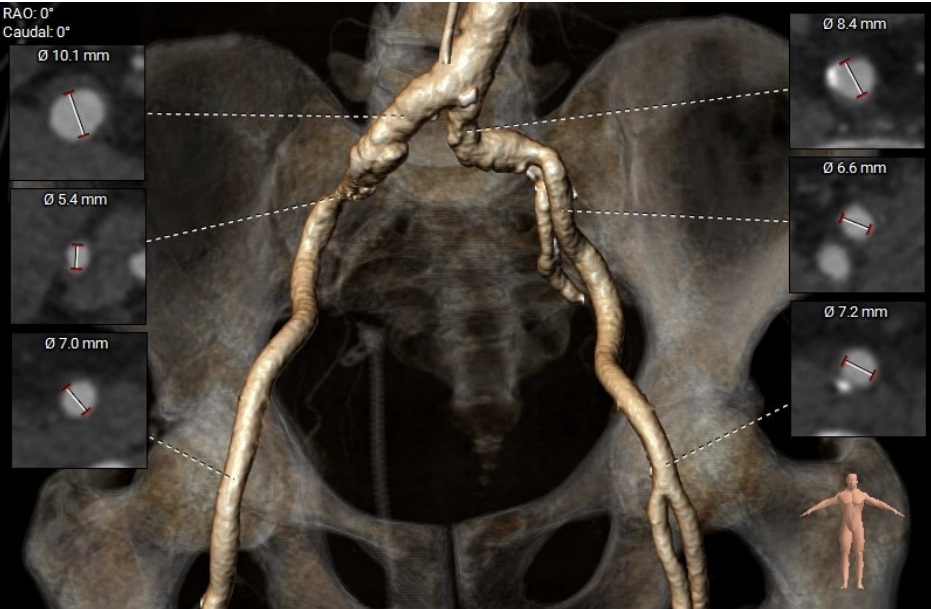

术前CT评估:

CT分析提示:TypeI型二叶瓣,左右瓣叶融合,瓣叶增厚,重度偏心性钙化,钙化位于无冠瓣叶及右无瓣叶交界处,且钙化延伸至LVOT2.5mm,舒张期可见瓣叶关闭不全间隙,右冠高度可,左冠开口平面可见瓣叶,左冠堵塞风险极高,心室略大,室壁厚度可,非横位心,升主动脉瘤样扩张,大血管走行自然,右侧髂总动脉血管细小。

瓣环直径29mm,LVOT直径31.1mm,typeI型瓣叶且偏心钙化位于无冠窦,按照常规瓣膜型号选择标准,但考虑患者两叶瓣,且左冠状动脉阻塞风险极高,downsize选择瓣膜型号,拟植入26mmVenus-A,备29mmVenus-A,高位释放,采用可回收输送系统,术中22mm球囊预扩张sizing后确定最终瓣膜型号选择。左冠预置支架保护。以左侧股动脉为主入路。